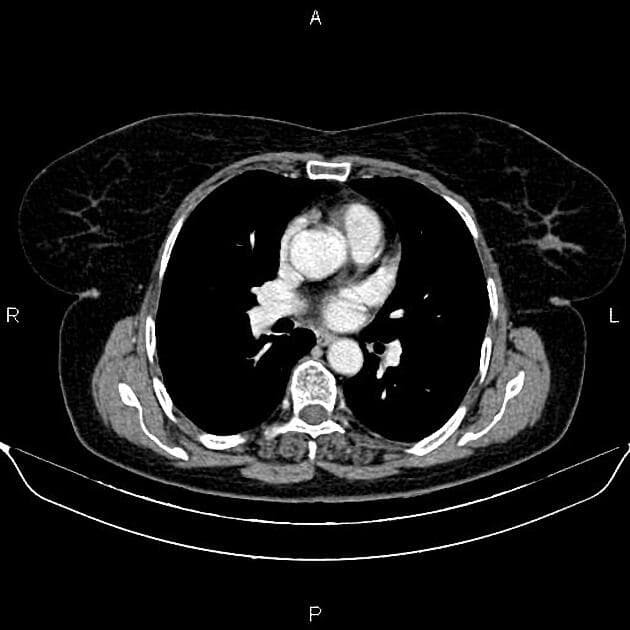

- "Bệnh Von Hippel-Lindau là một rối loạn di truyền đa hệ thống, đặc trưng bởi sự phát triển của các khối u lành tính và ác tính ở nhiều cơ quan."

- "Tổn thương tụy trong VHL thường biểu hiện dưới dạng nhiều nang không thông với ống tụy chính hoặc u nang tuyến nước."

- "Phân biệt với các tổn thương nang nhầy và u nhú nội ống tiết nhầy là rất quan trọng do nguy cơ ác tính."